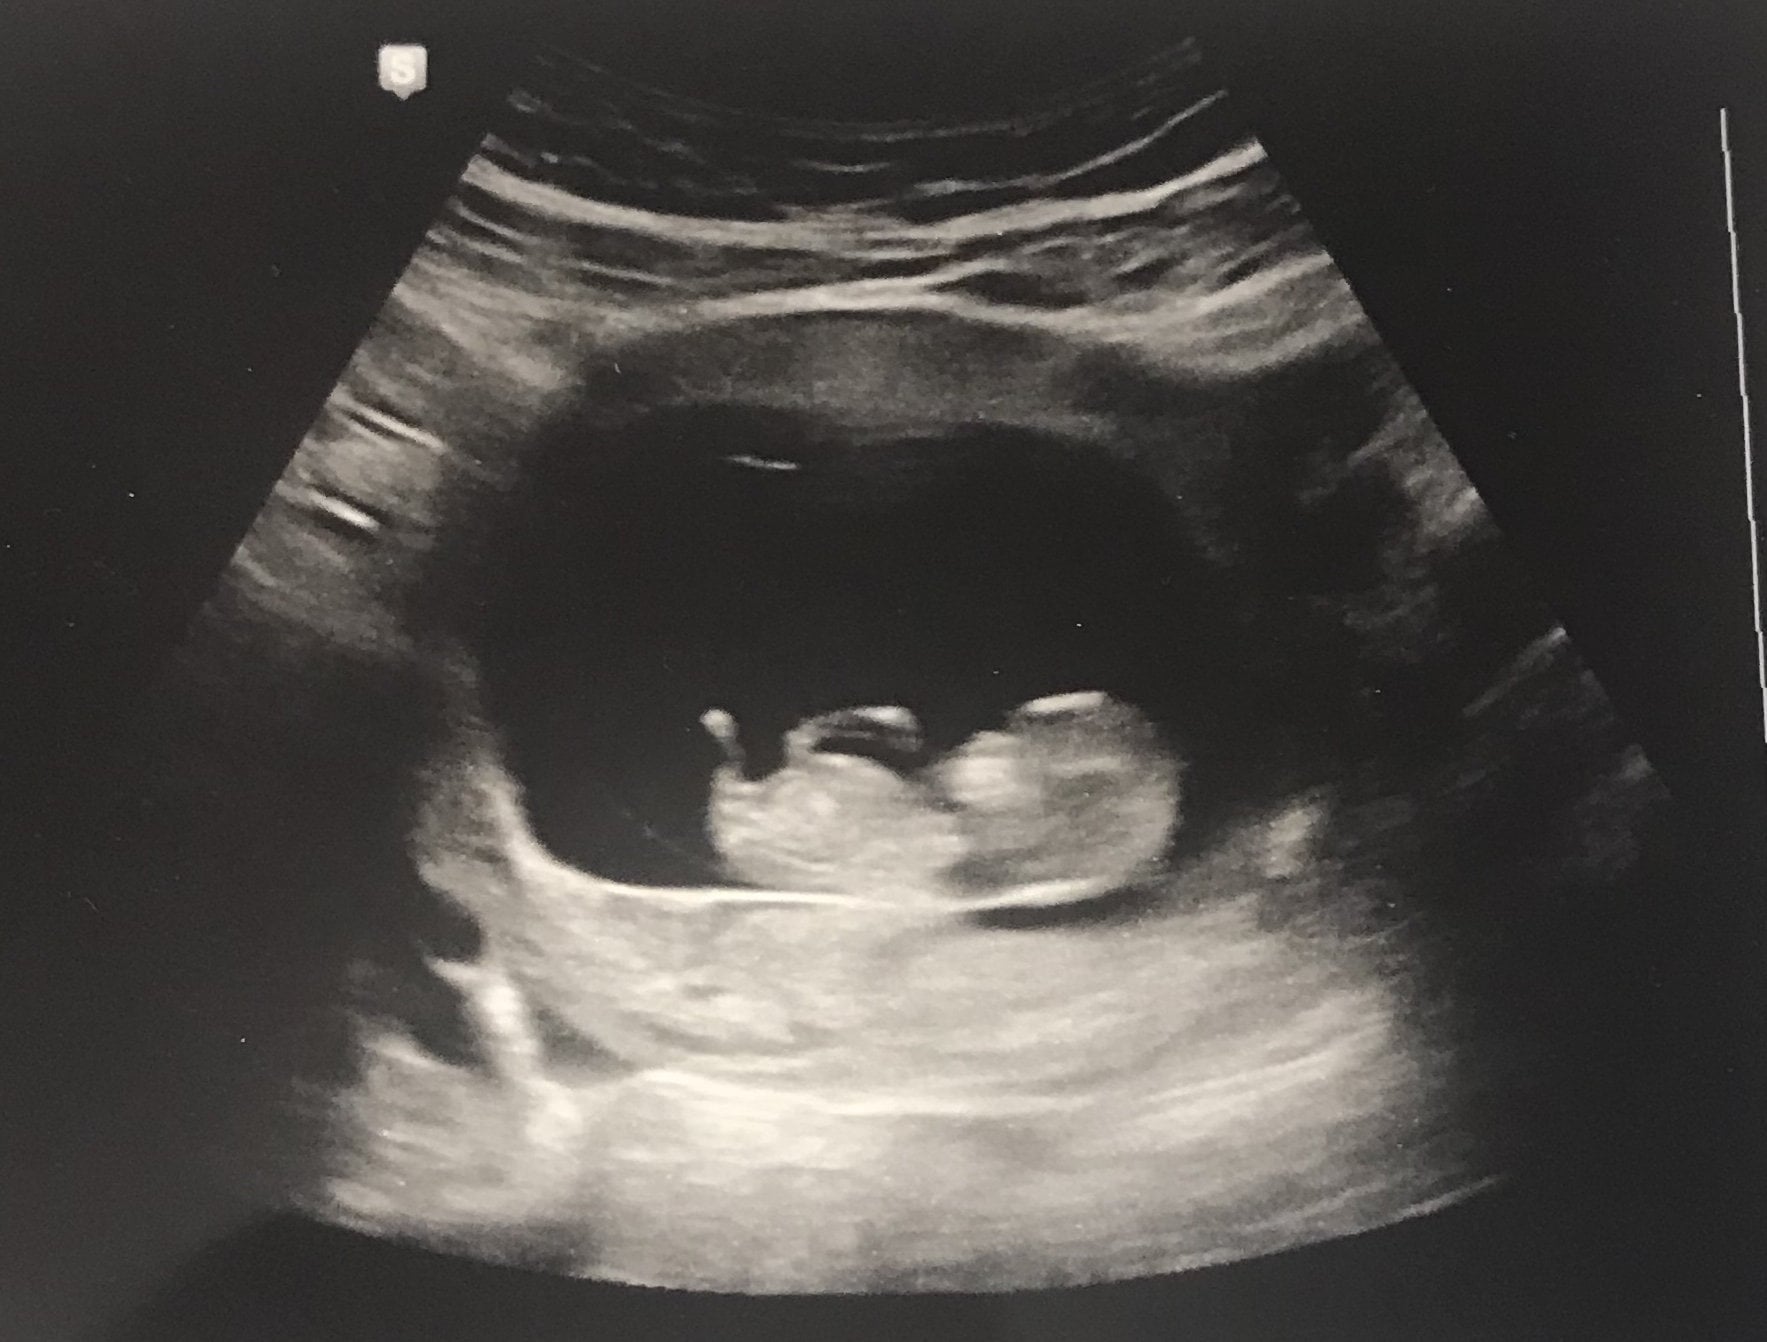

• 10 weeks and 1 day, so cute! Im in love